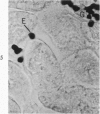

The beige mouse is a homolog of Chediak-Higashi syndrome, a disorder which is characterized by the presence of enlarged (anomalous) lysosomes in many cell types. In kidney, anomalous lysosomes are present in cells of the proximal convoluted tubules. In this study, the degradation of injected horseradish peroxidase (HRP) in lysosomes was studied in both the convoluted (S1-S2) and straight (S3) segments of the proximal tubules of beige and control (C57 B1) mice. Tissues were removed at intervals from 18 hours to 7 days after HRP injection. Peroxidase activity was visualized for light and electron microscopy by incubating sections in diaminobenzidine medium. No differences in the rate of degradation of HRP were demonstrable between anomalous lysosomes in S1-S2 cells of beige kidney and those in controls. In both animals, HRP was demonstrable in these lysosomes at 18 and 36 hours but not at 48 hours after injection. By electron microscopy, reaction product appeared as a flocculent precipitate distributed uniformly throughout the lysosome. In contrast to those of S1-S2 cells, lysosomes of beige S3 cells degraded HRP much more slowly than did those of control mice. In controls, HRP was demonstrable in S3 lysosomes at 18 hours but not at 48 hours after injection. In beige mouse kidney HRP was demonstrable in many S3 lysosomes at 48 hours, and it persisted in some lysosomes as long as 5 days after injection. These findings indicate that beige S3 lysosomes are defective in degrading protein. As reported recently, these lysosomes are also markedly enlarged and altered in content. They appear to arise as part of a renal lesion of unknown pathogenesis which is confined to the S3 segments of the proximal tubules. The slower rate of degradation of protein appears to be another manifestation of the alteration in these lysosomes.